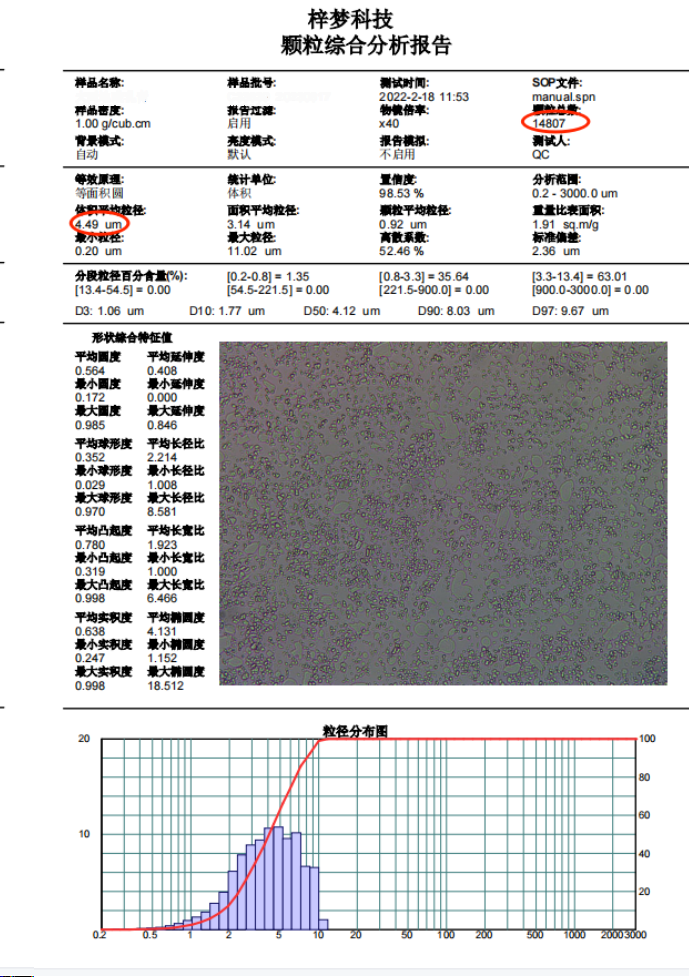

透皮乳膏粒度儀的測試報告如下:

從上圖報告中,可以得出分析的顆粒數量統計,平均粒徑,D10,D50,D90等值。可以得到置信度值,按照等效面積或者體積等給出用透皮乳膏粒度儀檢測凝膠的粒度分布。